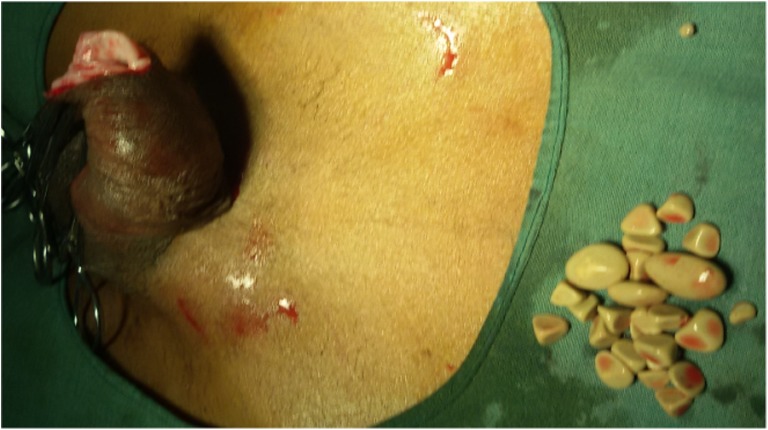

Fig. 2.

Calculi after extraction by circumcision

A 65-year-old man presented to our outpatient department with a mass at the tip of the penis with poor flow of urine since 6 months. Physical examination revealed phimosis (Fig. 1). The foreskin was felt separately from glans as a bag containing multiple calculi. Surprisingly, there was no urinary retention; however, his serum creatinine was 2.4 mg%. Abdominal sonography showed a stag horn calculus in the right kidney as well. His urinary as well as serum calcium was within normal limits. Patient underwent circumcision, which revealed 25 grayish white faceted calculi, largest measuring 1.5 cm and the smallest measuring 4 mm (Fig. 2). Calculi were made up of calcium phosphate as found on stone analysis. Subpreputial culture grew Escherichia coli organisms. Patient’s renal functions were normalized post surgery, and the patient is being evaluated for the management of right-sided stag horn calculus.